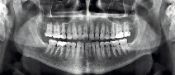

PARA AVALİAR O SEU PROBLEMA E TRAÇAR UM PLANO DE TRATAMENTO, BASTA ENVİAR-NOS FOTOS DA SUA BOCA E UM RAİO-X PANORÂMİCO. ENVİAREMOS GRATUİTAMENTE O RESULTADO DA AVALİAÇÃO DOS NOSSOS MÉDİCOS E TRAÇAREMOS UM PLANO DE TRATAMENTO.

FAÇA UM RAIO-X PANORÂMICO

NOSSOS CONSULTORES ONLINE ENVIARÃO SUAS FOTOS PARA AVALIAÇÃO DE NOSSOS ESPECIALISTAS E AJUDARÃO A ORGANIZAR SEU TRATAMENTO PASSO A PASSO.